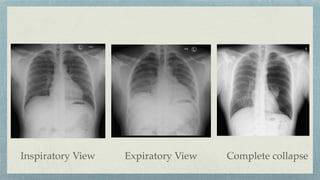

Pneumothorax

Clearly de

fi

ned line.

Upper part of the line is curved at lung

apex.

Absence of lung markings.

Erect xray in full expiration

CT- Best modality

Supine:-

Hyperleucent upper quadrant of

abdomen

Lateral costophrenic angle…

Deep Sulcus Sign

Sharply outlined dome of

diaphragm

Inspiratory View Complete collapse

Expiratory View